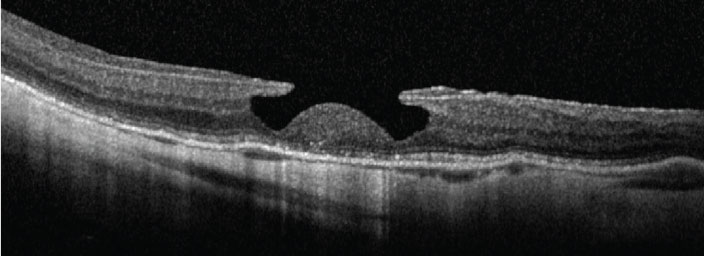

10. Omega sign (II)

Retention of perfluorocarbon (PFCL) bubbles following PPV can lead to the subsequent accumulation of PFCL in the subretinal space. This can result in a bubble with a dome-shaped appearance, called the omega sign (Figure 10).

If this occurs in the subfoveal space, the PFCL should be removed to avoid long-term damage to the photoreceptors.13

![]() |

|

Figure 10. Omega sign, caused by retention of perfluorocarbon bubbles. (Courtesy Nicolas Yannuzzi, MD, and Jayanth Sridhar, MD) |